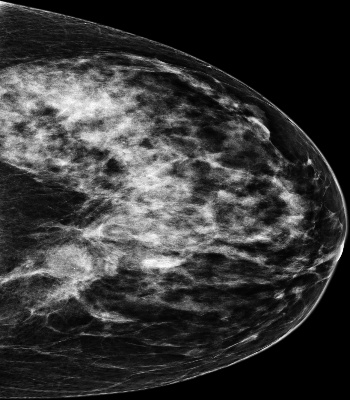

Mammography is used as a standard screening procedure for the potential patients of breast cancer. Over the past decade, it has been shown that deep learning techniques have succeeded in reaching near-human performance in a number of tasks, and its application in mammography is one of the topics that medical researchers most concentrate on. In this work, we propose an end-to-end Curriculum Learning (CL) strategy in task space for classifying the three categories of Full-Field Digital Mammography (FFDM), namely Malignant, Negative, and False recall. Specifically, our method treats this three-class classification as a "harder" task in terms of CL, and create an "easier" sub-task of classifying False recall against the combined group of Negative and Malignant. We introduce a loss scheduler to dynamically weight the contribution of the losses from the two tasks throughout the entire training process. We conduct experiments on an FFDM datasets of 1,709 images using 5-fold cross validation. The results show that our curriculum learning strategy can boost the performance for classifying the three categories of FFDM compared to the baseline strategies for model training.